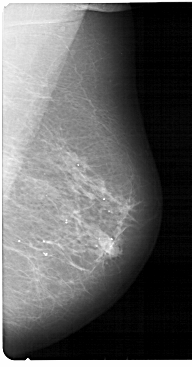

A_1868_1.RIGHT_CC

RIGHT_CC LINES 5491 PIXELS_PER_LINE 2836 BITS_PER_PIXEL 12 RESOLUTION 43.5 NON_OVERLAY